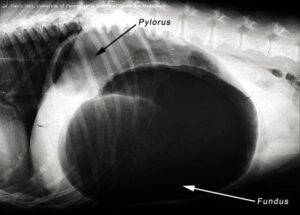

Устройство и механизм работы желудка

Желудок этого млекопитающего – это мешочек, который расположен таким образом, что самая широкая его часть находится спереди, соответственно сзади он сужен. С одной стороны желудка расположен вход пищевода, а с другой – выход в кишечник. Между ними находится «малая кривизна». Круглая мышечная складка при входе пищевода расположена таким образом, чтобы для проталкивания пищевых масс совершалось усилие, а употребленный вместе с едой воздух выталкивался.

Желудок в пустом состоянии расположен под левым ребром, но, наполняясь, он растягивается и доходит до нижней стенки живота. Именно эта способность влияет на возможность возникновения заворота кишок (перекручивание желудка и селезенки вокруг пищевода).